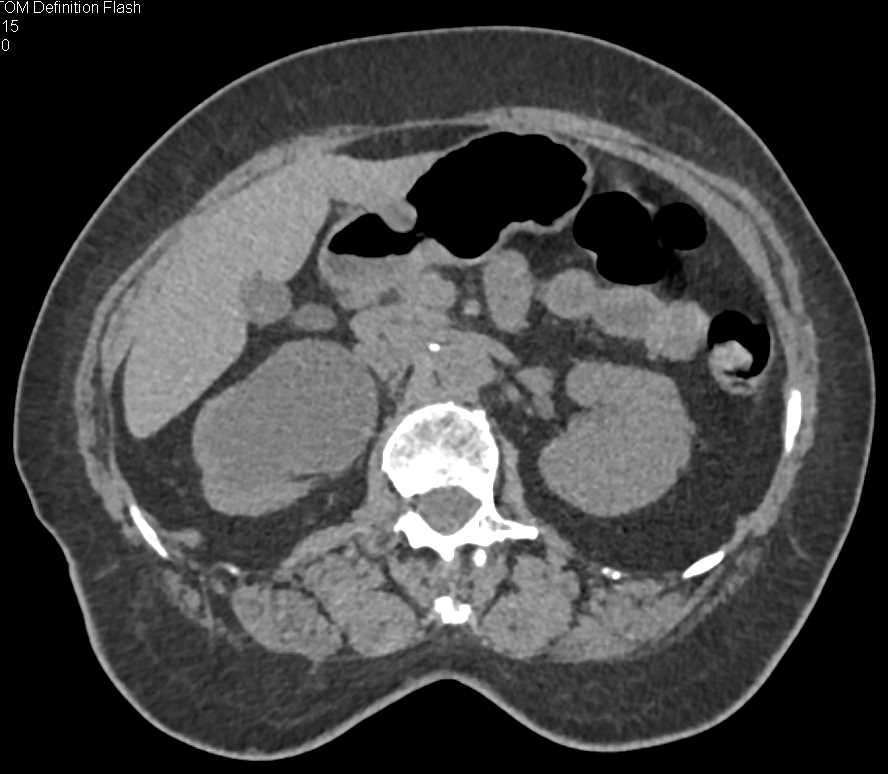

Xanthogranulomatous Pyelonephritis (XGP) Right Kidney